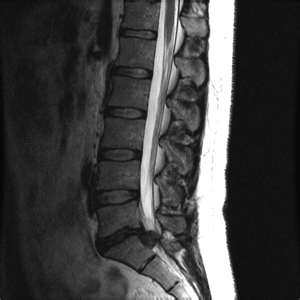

Эти симптомы являются основными признаками дегенеративного заболевания. На изображении представлен рентгеновский снимок пояснично-крестцового отдела, пораженного остеохондрозом.

На основании клинического осмотра и тщательного сбора анамнеза устанавливается предварительный диагноз. Затем проводятся дополнительные инструментальные исследования для подтверждения или опровержения предположений врача.

Важно! Опасность данного заболевания заключается в том, что оно может долгое время развиваться без явных симптомов, что часто приводит к переходу в хроническую форму. Поэтому при первых проявлениях остеохондроза крайне важно незамедлительно обратиться к врачу для проведения МРТ, УЗИ, ЭКГ и лабораторных анализов.